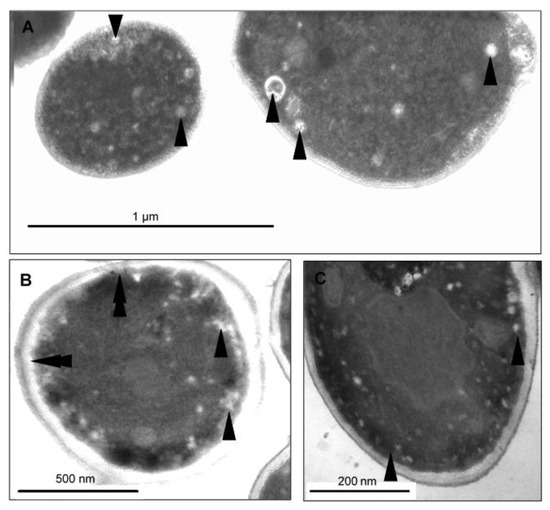

Figure 7.

TEM micrographs of C. albicans SZMC 1423 treated with a sub-lethal concentration of CAPE exhibit different markers of cellular deterioration. (A) Severe cell wall distortion. (B,C) Appearance of enlarged lysosomes was rather frequently detected (arrowheads). (D) Isolation membranes precondition of cytoplasm fragmentation (arrowheads). (E,F) Nucleus fragmentation and marginal condensation (arrowheads).